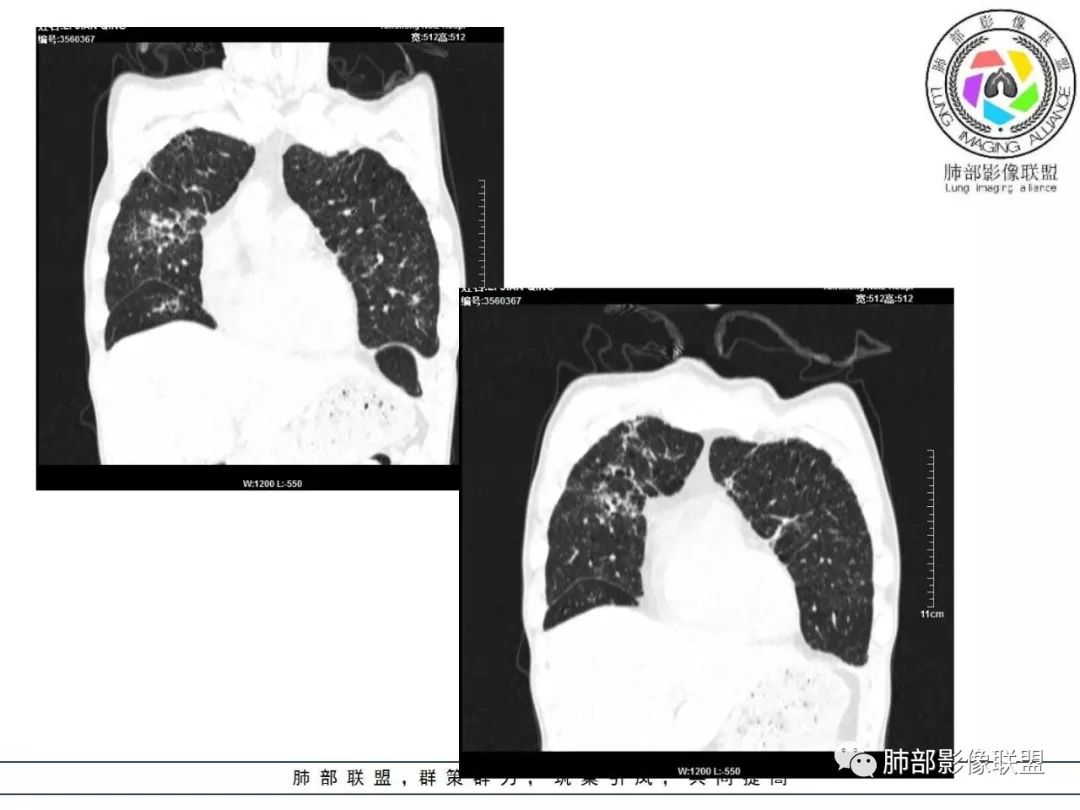

双肺间质性病变,中央间质增厚,胸膜下间质增厚,左侧胸膜肥厚,胸廓变小,肋间隙变窄。

胸部CT:两肺弥漫病灶,磨玻璃影,少许实变,部分累及胸膜,磨玻璃区可见囊?少许胸腔积液,两肺可见结节,支气管血管束增粗,小叶间隔增厚,支气管走形有扭曲扩张,可见纤维化。气肿、大泡。考虑:感染性病变,PCP?查下HIV,CD4,G等。鉴别结核、结缔组织病肺浸润。

55多男性,发热为主诉,体温38℃-39℃多,午后及夜间发热为主,峰值40℃,伴黄痰,CRP高,血糖正常,胸部CT:两肺弥漫病灶,磨玻璃影,少许实变,部分累及胸膜,两肺可见结节,似可见树芽,支气管血管束增粗,小叶间隔增厚,见肺气肿、大泡。考虑感染性病娈,肺结核可能性大。

患者中年男性,发热1月,体温38℃-39℃,峰值40℃,无畏寒、寒战,伴黄痰,CRP升高明显,降钙素原稍升高,血沉、血糖正常。胸部CT:两肺弥漫病变,磨玻璃影+点片渗出,部分累及胸膜,磨玻璃区边界清楚,少许胸腔积液,两肺支气管血管束增粗,小叶间隔增厚,部分支气管走形有扭曲扩张,可见肺气肿、右肺尖肺大泡及部分纤维化改变。综合考虑:感染性病变。结核或PCP可能性大,鉴别风湿免疫、结缔组织疾病肺浸润和腺癌等恶性病变。

胸部CT:两肺弥漫病灶,中央间质分布为主,部分位于胸膜及叶间裂旁,磨玻璃影,斑片影,部分实性结节,肺气囊,支气管血管束增粗,小叶间隔增厚,叶间裂不均匀增厚,支气管走形有扭曲扩张,可见纤维化、气肿、大泡。考虑:LIP加MALT。鉴别PLCH、PCP、结核、结缔组织病肺浸润。

病灶呈片状磨玻璃密度影,呈典型的烟花征。磨玻璃影密度偏高,有网结节样改变,与正常肺实质分界清楚,且常见相对高密度的勾画。

病变一般沿血管支气管束分布或小叶分布,一般上肺多于下肺(这与常见继发性肺结核分布相若)。

2. 肺气肿背景(小叶中心性肺气肿);双肺多发病灶整体沿血管支气管束及胸膜下分布,以上叶及下叶背段分布为主,有实变及GGO,边界清楚,有树芽,小叶间隔及中央间质增厚,叶间裂见到多发结节,部分支气管不规则牵拉扩张,提示病灶纤维化明显,结合临床病史,考虑病灶为间质性感染,肺门及纵隔内有钙化淋巴结,小叶间隔结节,考虑淋巴道增值性疾病可能,综合常规要怀疑间质性肺结核。